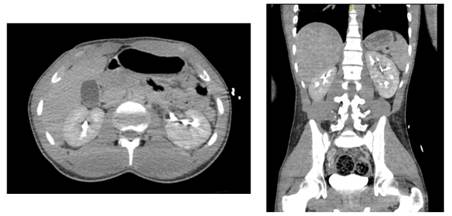

Case 1

A 36-years-old male with renal polycystic disease, presented to the ER with abdominal pain and gross hematuria after falling from an e-scooter and having an abdominal traumatism in the right flank against the e-scooter handlebar while riding it at 20km/h. Physical examination revealed pain with the right flank palpation without peritoneal irritation signs. A CT scan was performed revealing a hemorrhagic cyst with no other alteration (Figure 1 & 2). Being classified as a AAST grade I, the patient received conservative management, then went home with a normal glomerular filtration rate (GFR) and hemoglobin with an order for a US for the ambulatory follow up within a month.